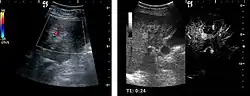

Hepatic hemangioma (2D). The lesion is located in the left hepatic lobe. Note precise delineation, their increased echogenity and the heterogeneous internal structure.

It is the most common liver tumor with a prevalence of 0.4 – 7.4%. It is generally asymptomatic but also can be associated with pain complaints or cytopenia and/or anemia when it is very bulky. It is unique or paucilocular. It can be associated with other types of benign liver tumors. Characteristic 2D ultrasound appearance is that of a very well defined lesion, with sizes of 2–3 cm or less, showing increased echogenity and, when located in contact with the diaphragm, a "mirror image" phenomenon can be seen. When palpating the liver with the transducer the hemangioma is compressible sending reverberations backwards. Doppler exploration reveals no circulatory signal due to very slow flow speed. CEUS investigation has real diagnosis value due to the typical behavior of progressive CA enhancement of the tumor from the periphery towards the center. The enhancement is slow, during several minutes, depending on the size of hemangioma and on the presence (or absence) of internal thrombosis. During late (sinusoidal) phase, if totally "filled" with CA, hemangioma appears isoechoic to the liver. Deviations from the above described behavior can occur in arterialized hemangiomas or those containing arterio-venous shunts. In these cases, differentiation from a malignant tumor is difficult and requires other imaging procedures, follow up and measurements of the tumor at short time intervals.[4]